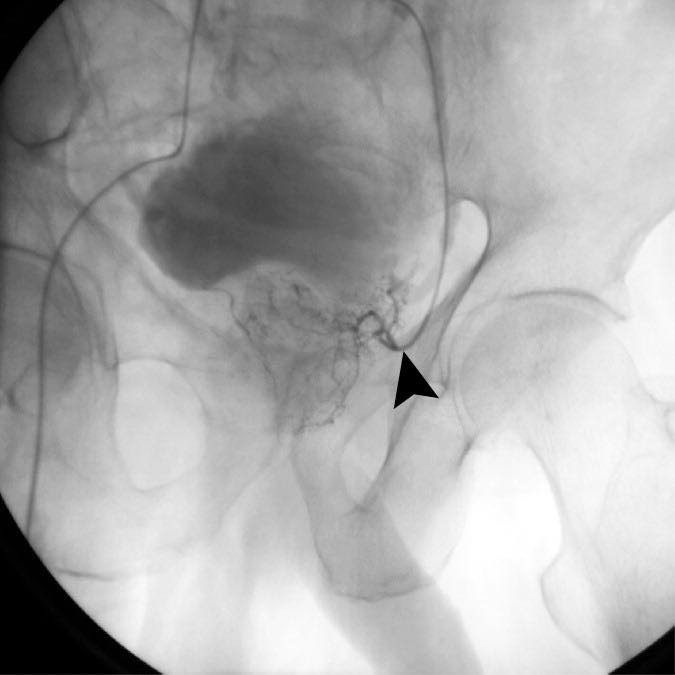

• يتم الدخول عبر شريان الفخذ أو شريان اليد (الرسغ)

• باستخدام الأشعة السينية، يُوجَّه قثطار دقيق جداً إلى الشرايين المغذية للبروستاتا

• تُحقن جزيئات دقيقة (مواد انصمامية) لإغلاق هذه الشرايين جزئياً

• مع الوقت، يقل حجم البروستاتا ويخف الضغط على مجرى البول